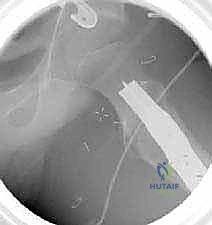

3. إدخال السلك الدليلي (Guide Wire)

تحت توجيه الأشعة السينية المباشرة داخل غرفة العمليات (C-arm)، يقوم الدكتور هطيف بإدخال سلك دليلي في عنق ورأس عظم الفخذ بالزاوية الصحيحة والمحسوبة بدقة.